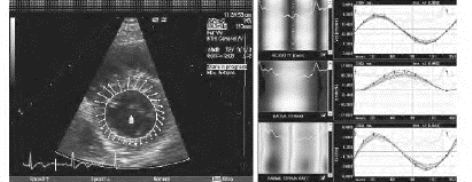

5.速度向量成像(velocity vector imaging,VVI)和斑点追踪技术(speckle tracking imaging,STI) VVI是通过采集原始二维像素的振幅及相位信息,对心肌运动自动追踪,得到带有心肌运动方向及速度大小的动态向量图,通过分析向量大小和方向得到心肌运动的速度、应变、应变率等信息(图19-6)。STI技术是使用区块匹配和自相关搜索算法测量组织运动,它把心肌组织看成无数个像素,在心动周期中逐帧扫描某个像素的位置,追踪心肌组织内的高回声斑点,并与最初的位置进行比较来观察心肌运动(图19-7)。这两种技术均不受声束方向与组织运动夹角的影响。可用于测量心肌心脏短轴及长轴各节段的二维应变、应变率和局部心肌旋转角度的变化,克服了组织多普勒技术仅能量化心肌长轴方向应变的局限性,实现了无角度依赖地评价心肌运动。可在纵向、径向和环向上定量测量局部心肌运动的力学参数,是研究心肌结构力学、分析整体与局部心功能和评价心肌收缩同步性等的新技术。

图19-6 VVI显示左室短轴心肌运动向量图及速度、应变和应变率曲线

图19-7 STI显示左室短轴各节段心肌运动的径向速度和应变曲线